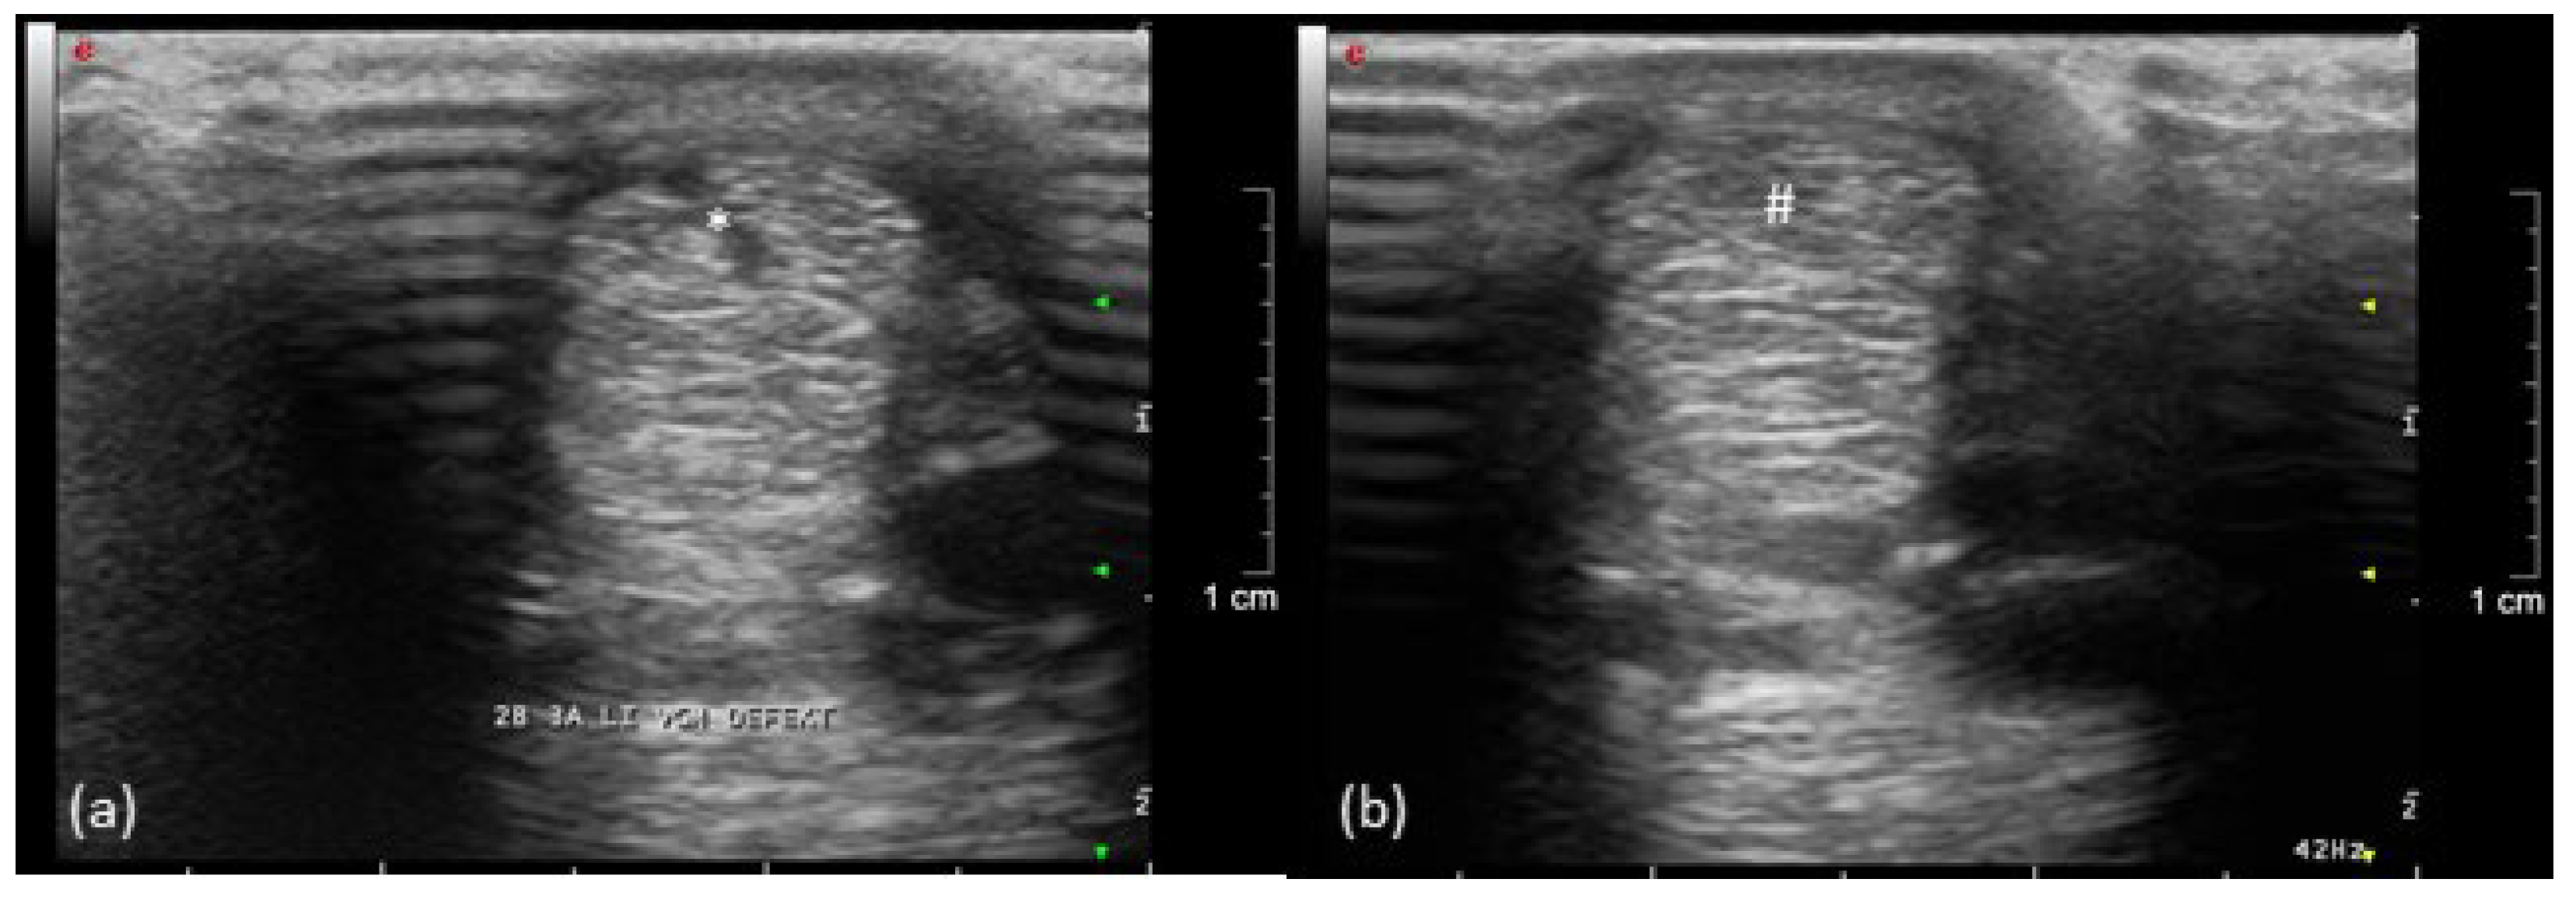

Figure 4.

Ultrasonographic image of the left forelimb of a pony, left is lateral: (a) acute (*) and (b) healing (#) tendon lesion of the SDFT (9 weeks after injection of collagenase).

A mild swelling occurred for several weeks in the bone marker regions with no other signs of inflammation or pain during palpation. During the lameness examination, in the 14th week, the implantation sites were no longer circumferentially enlarged. After walking and trotting on the treadmill during the first FluoKin measurement (“FluoKin 1”), a diffuse swelling of the lateral aspect of the metacarpal region appeared for three days. Two weeks after injection of collagenase, the pony showed a lameness score of 2 out of 5 in the left forelimb during walk and trot but maintained an even weight distribution while standing. The corresponding ultrasound examination of the left forelimb SDFT showed an acute, hypoechogenic tendon lesion in the center of the mid-metacarpal region with a slightly enlarged diameter (Figure 4). In the right forelimb, no signs of tendonitis were seen in the ultrasound in the 7th week. Five weeks after injection of collagenase, no lameness but a slightly more careful use of the left forelimb was observed during walk. There was a lameness score of 1 out of 5 during trot. Nine weeks after injection of collagenase, no gait abnormalities during walk and a barely noticeable lameness score of 1 out of 5 during trot were detected. Within the corresponding ultrasound examination in week 14, hyperechogenic lines in the tension direction were demonstrated in the remaining hypoechogenic lesion (Figure 4). Fifteen and thirty-three weeks after injecting collagenase, no lameness could be observed. The final ultrasound examination in the 37th week showed normal tendon tissue. The beads did not slip out of the tendon over the course of the study. The proper location of all beads in the tendon tissue was verified both with CT in week 7 and repetitive ultrasound examinations (4th week, 7th week, 14th week, and 37th week).